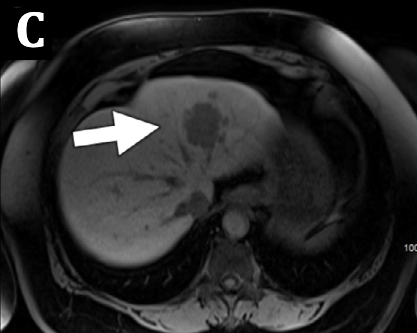

#CaseOfTheDay 🧠 📍 58-year-old male presenting with fatigue and right upper quadrant discomfort. MRI shows a left hepatic lobe mass. 💭 Drop your diagnosis below! #LiverImaging #MRI #Radiology #MedEd #RadRes #HepaticTumor #CaseChallenge #MedTwitter

✅ Answer: Hepatic Angiosarcoma 🧠 Key findings/phase: Arterial: Heterogeneous rim hyperenhancement Portal venous: Progressive centripetal enhancement Hepatobiliary: Hypointense + T2 signal hyperintity More info https://t.co/svs1qaqG2n #Radiology #MedEd #RadRes #MedTwitter